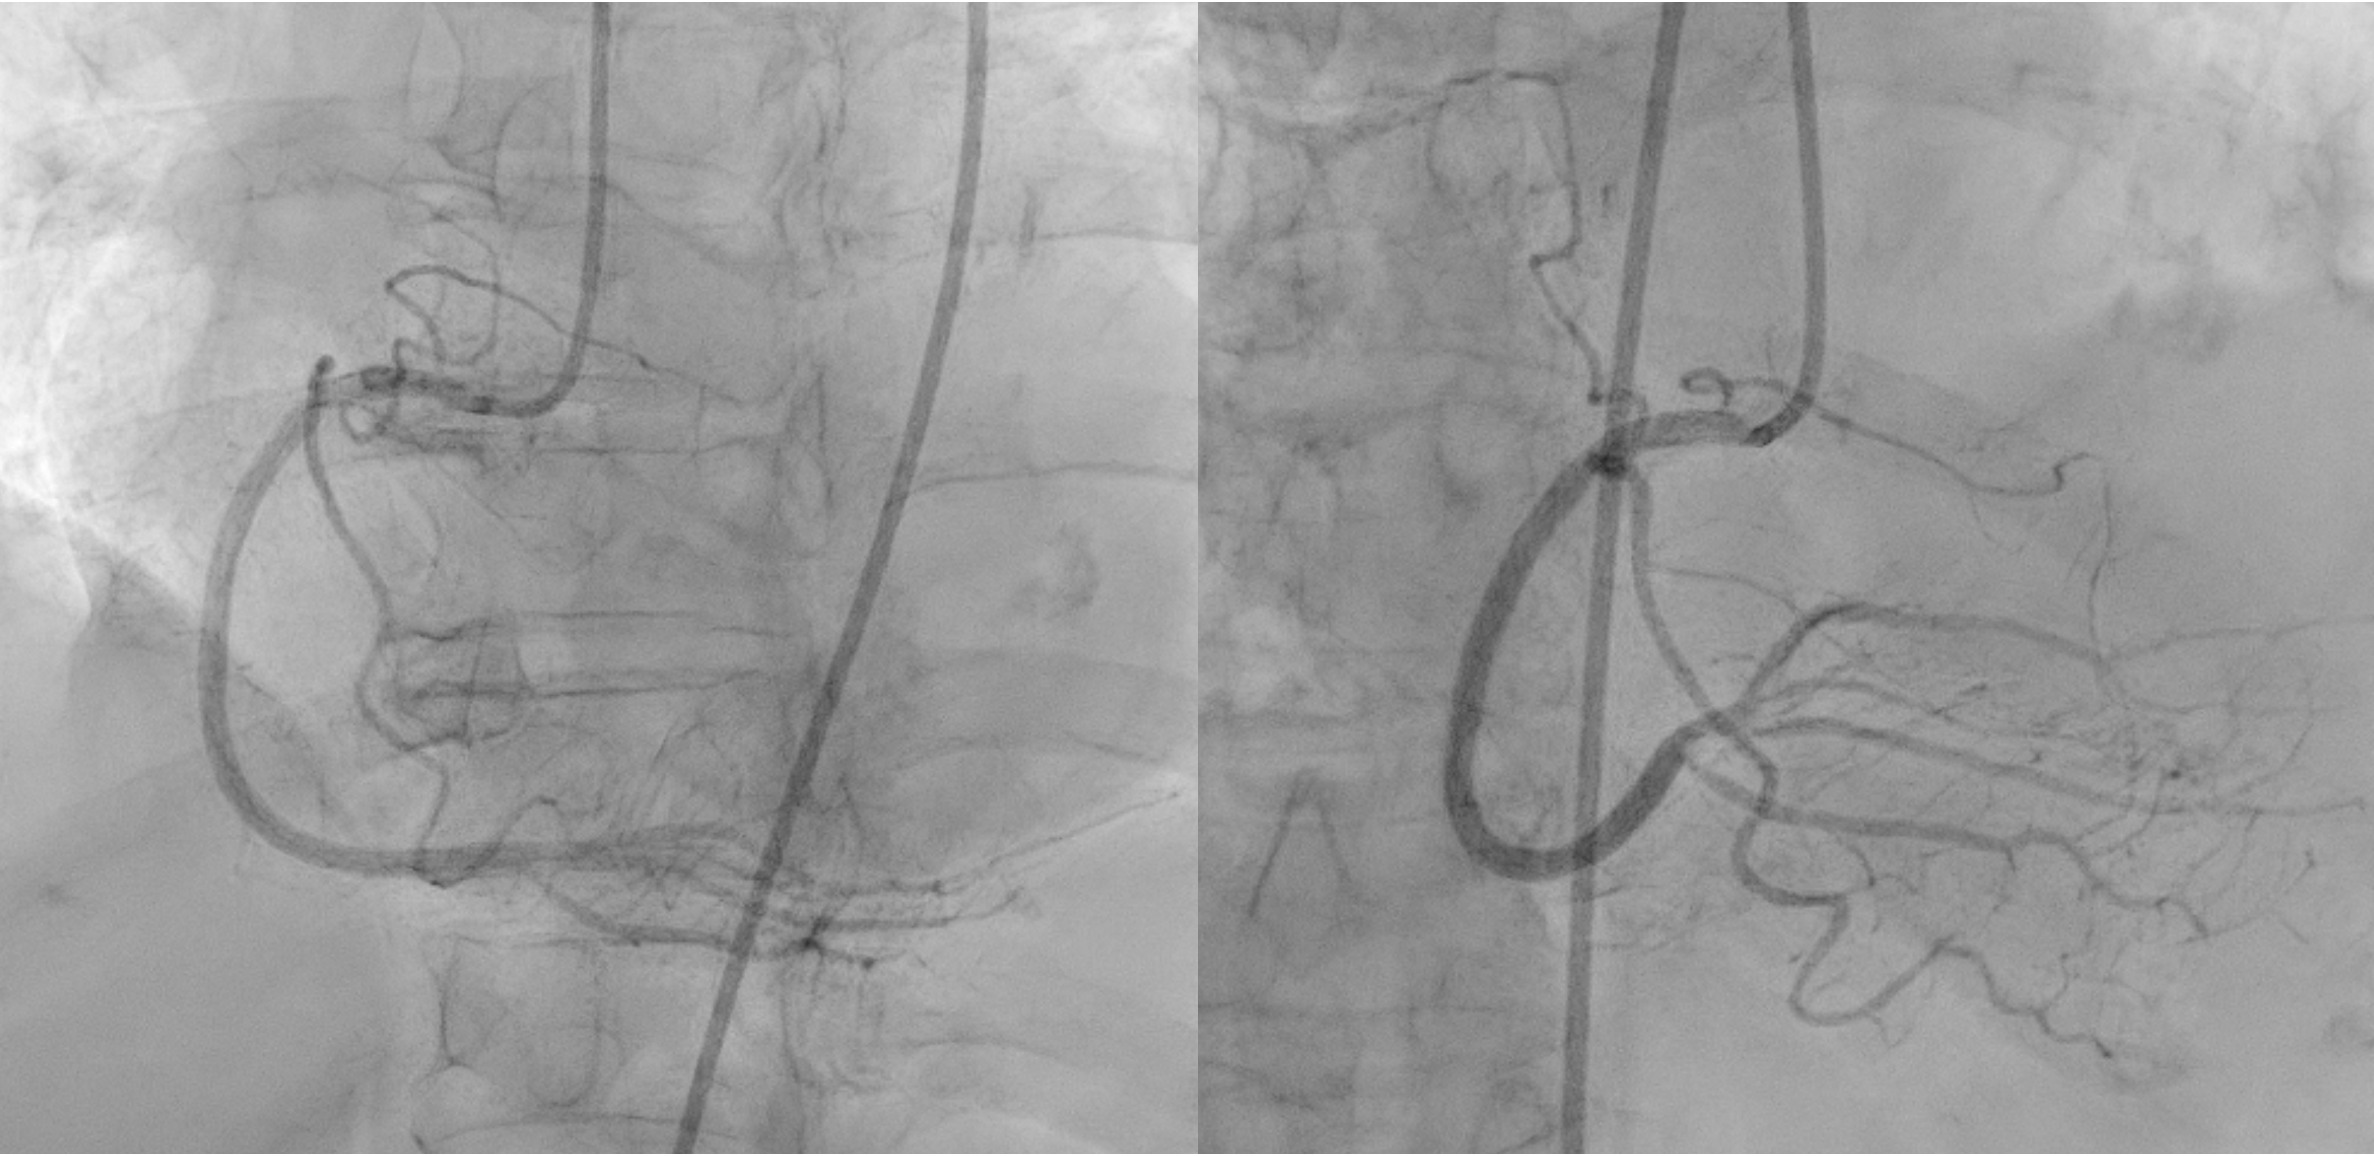

Procedural Step

Based on angiographic and IVUS findings, the lesion was prepared using a scoring non-compliant (NC) balloon (ScoreFlex) 2.5 mm ¡¿ 15 mm, inflated from the distal LAD to distal LM at a maximum of 18 atm. A first drug-eluting stent (DES) Cre8 2.75 mm ¡¿ 46 mm was deployed from the proximal to distal LAD, followed by a second DES (Combo Plus) 3.5 mm¡¿ 38 mm from the distal LM to the proximal LAD with overlap. During withdrawal of the stent balloon, the guiding catheter (XB 3.5/ 7 Fr) advanced too deeply, resulting in crushing of the proximal portion of the Combo Plus stent. Angiography showed that the crushed stent no longer adequately covered the distal LM lesion. Attempts were made to reopen the crushed segment using a series of semi-compliant balloons (Sapphire II Pro): 0.85 mm ¡¿ 15 mm, 1.0 mm ¡¿ 15 mm, and 2.0 mm ¡¿ 15 mm, each inflated to a maximum 20 atm. A non-compliant (NC) balloon 4.5 mm ¡¿ 8 mm was then used to dilate the stent struts. A third DES (Ultimaster Tansei) 3.5 x 24 mm was deployed from the ostial LM to the proximal LAD, overlapping the previously crushed stent. Proximal optimization (POT) was performed in the LM using a 4.5 mm ¡¿ 8 mm NC balloon inflated to 22 atm. Final angiography showed a satisfactory result with minimal residual stenosis in the distal LM. The final IVUS assessment could not be perfromed due to damage to the IVUS catheter